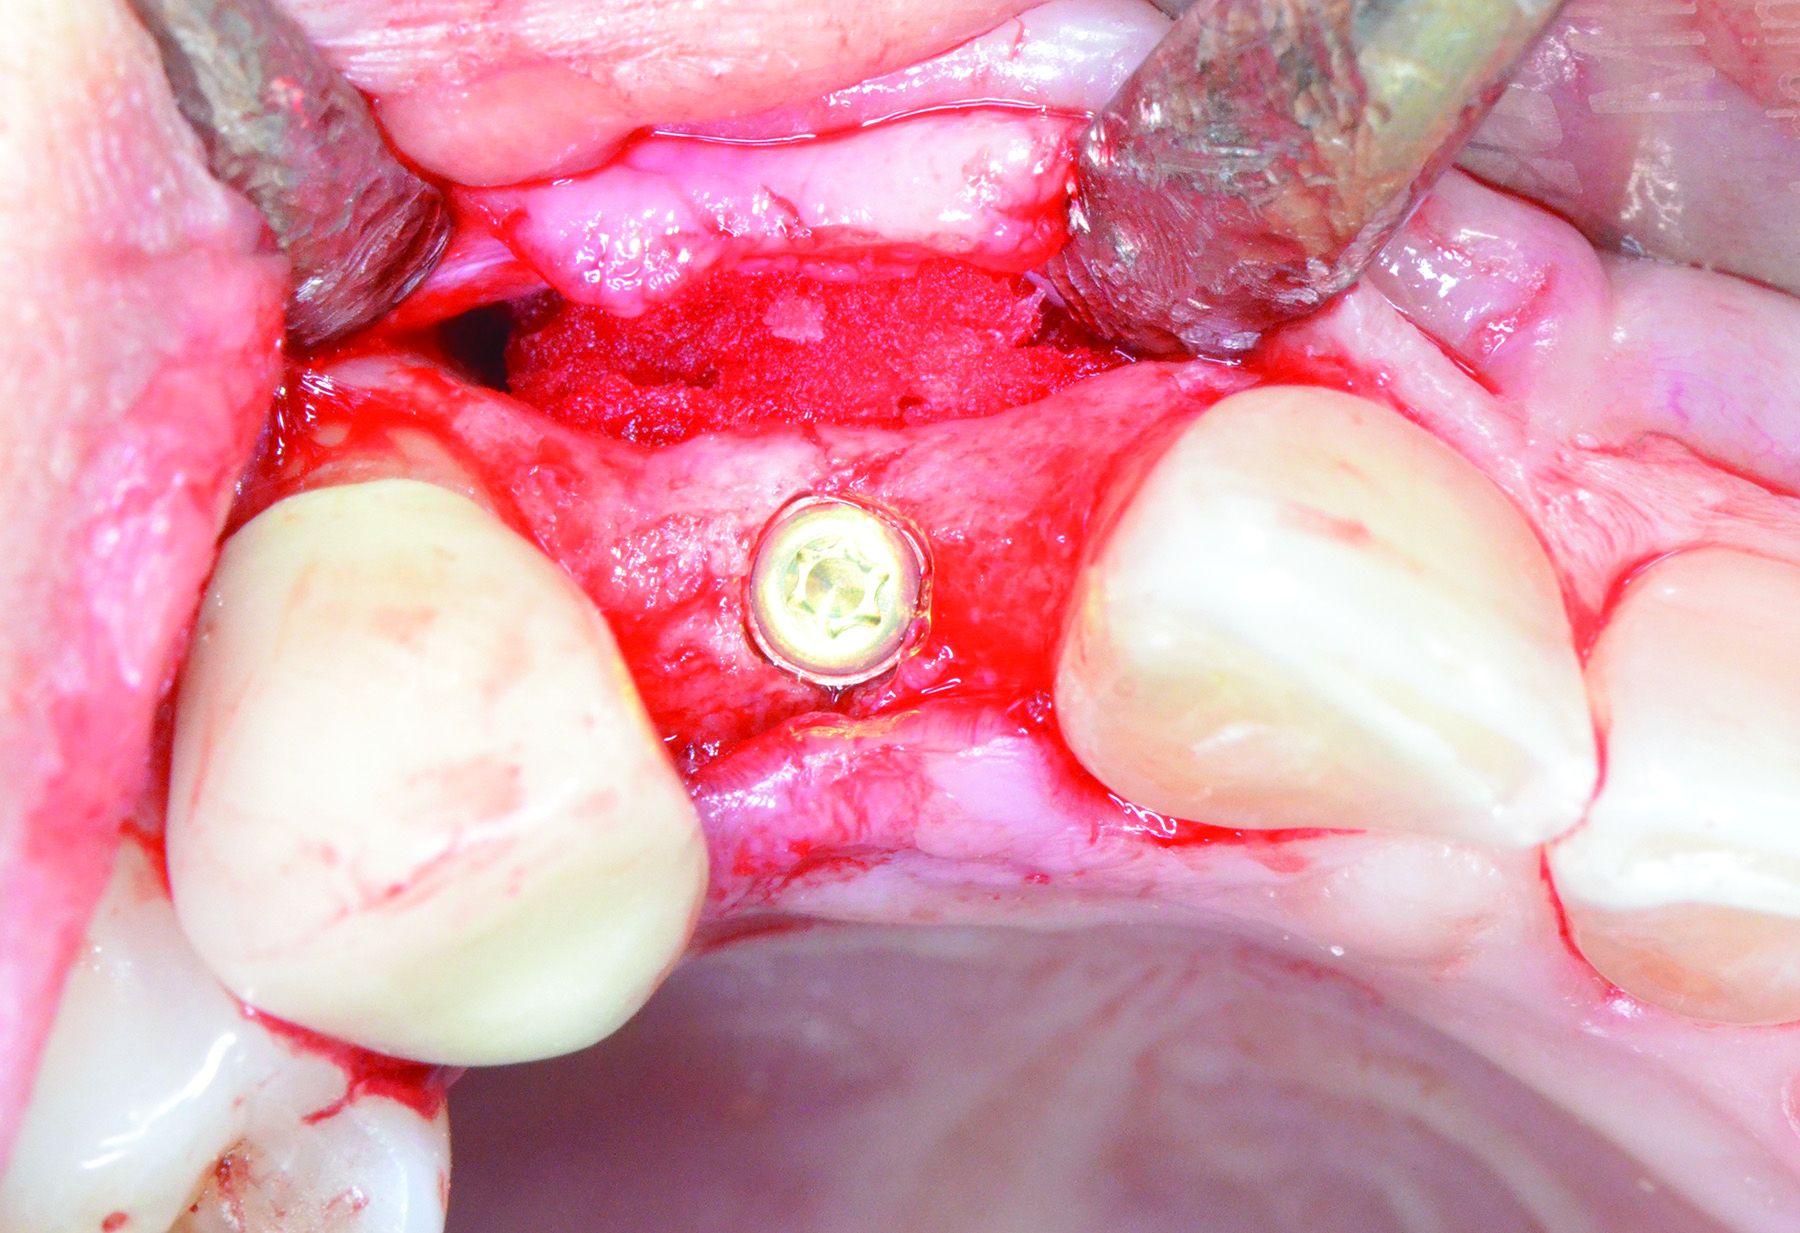

Fig 12 through Fig 14. Example of increasing MT with a roll technique. Fig 12: incision design for implant placement with a healing abutment placement and to enhance MT; the recipient site is prepared on the buccal side; the palatal aspect of the flap will be rolled to the buccal recipient site; Fig 13: insertion of roll of tissue taken from the palatal aspect of the flap; Fig 14: implant placement with healing abutment.

Figure 12

Figure 13

Figure 14

When a lack of KMW is noted, suggested treatments may include the use of an apically positioned flap (APF)20 (Figure 6 through Figure 8) or a combination of APF with an FGG (Figure 9 through Figure 11) or tissue alternatives.21 Because of the nature of the recipient site preparation for an FGG or tissue alternative, such as ADM, AXDM, or CM, there is a risk of wound dehiscence and a potential negative effect on the healing of the bone augmentation or on osseointegration if the grafting is done at the time of ridge augmentation or implant placement. Therefore, the preferred treatment time for increasing KMW with an FGG, ADM, AXDM, or CM is either prior to implant placement or after healing of the implant at the healing abutment connection (Table 1). MT can be increased using the roll technique (Figure 12 through Figure 14)22,23 or by adding a CTG (Figure 15 and Figure 16), ADM, AXDM, or CM (Figure 17 and Figure 18), either at the time of implant placement or healing abutment connection (Table 1).24,25